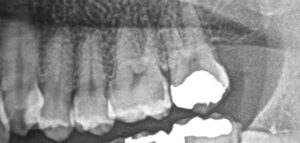

レントゲン撮影を行ったところ、大きな虫歯が出てきました。